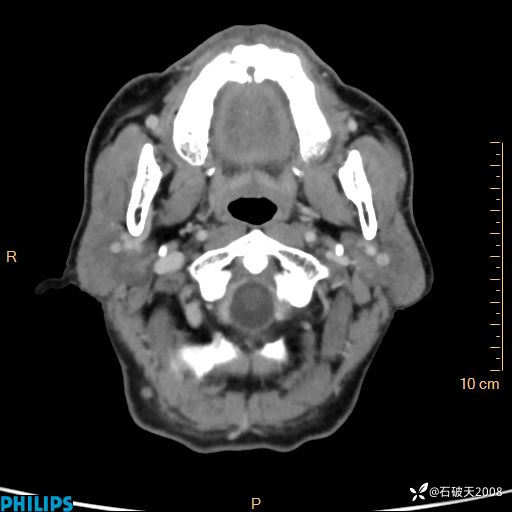

冠状位